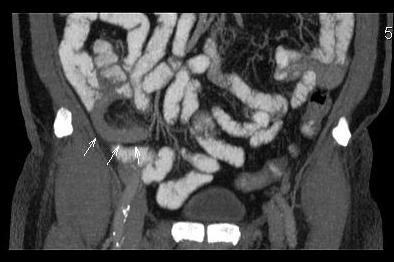

- Острый аппендицит, КТ MPR coronal

- AA Cor.jpg (18.44 КБ) 1340 просмотров